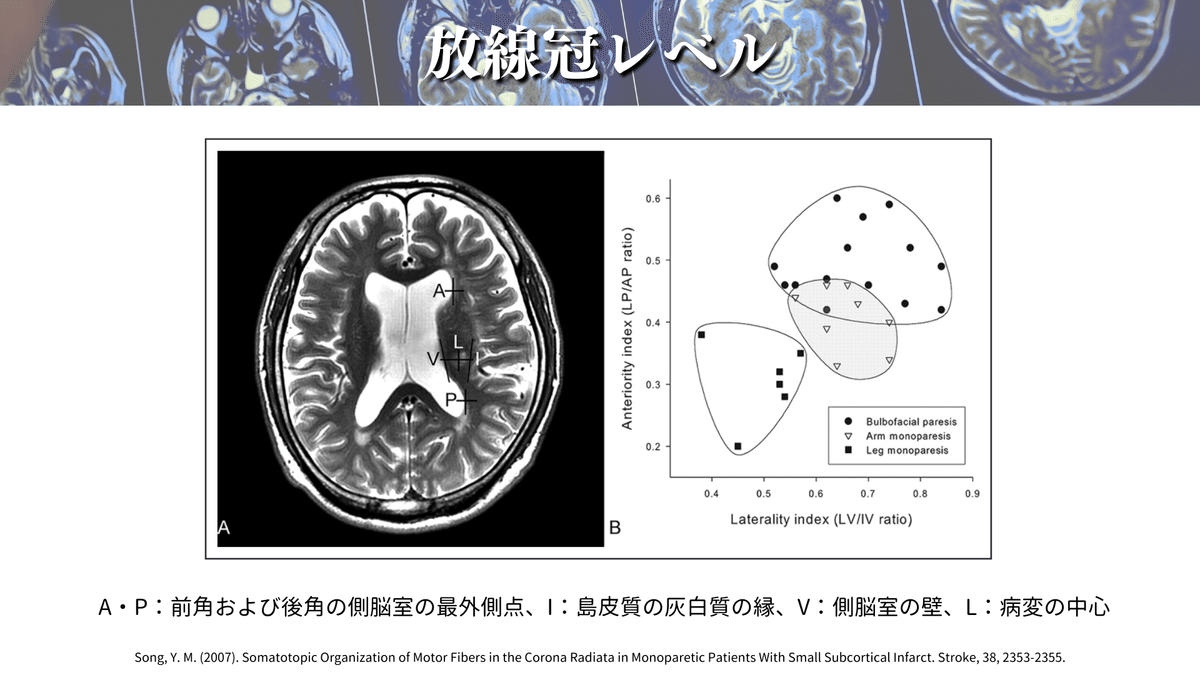

放線冠レベルの解説をしている論文は他にも多くあるので、オススメを紹介していきます✨

側脳室の前角や後角、側脳室の壁や島の縁などの距離から、口顔や上下肢のCSTの位置を計算する方法があります☝️

これによると、最も前外側に位置するのが口顔の線維であり、最も後内方に位置するのが下肢の線維ということが一目でわかりますね😳

これらのことから、大体この辺りを通るのかなということがわかったのではないでしょうか?🕵️(上図)